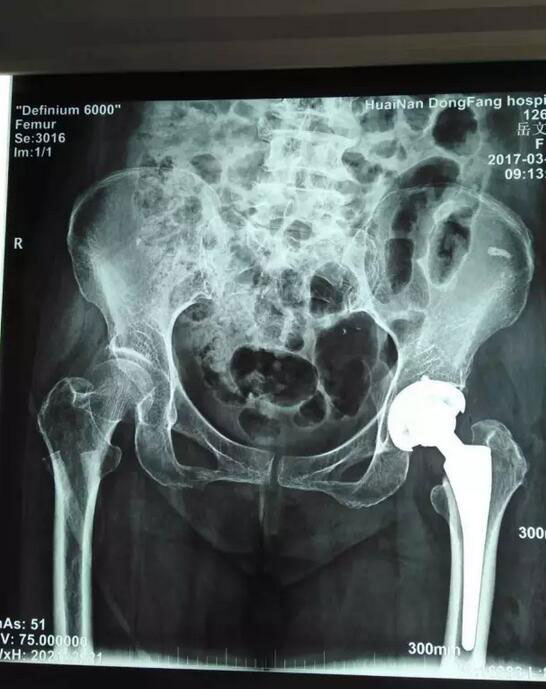

术前术后对比

岳老太太今年已经70岁,因为股骨颈骨折,需要进行全髋关节置换手术。经过总院骨科团队慎重研究并向老太太家属沟通后,3月6日接受了这一最新理念的手术,也是总院骨科开展的第二此类手术。手术由鲁木主任亲自主持,顺利结束后老人安全返回病房。术后第二天,老太太就可以下床并自如行走、弯腰,甚至可以自己穿上袜子,岳老太太的老伴对此惊喜不已,连连对鲁木主任和医护人员们表示感谢。在他的印象中,动了这么大的一个手术,最少要在床上躺上十天半个月,没想到现在恢复的这么快,这么好!一周后,老人恢复良好,顺利出院。